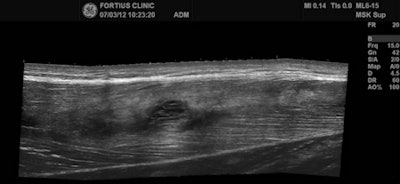

the musculotendinous junction. Note the feathery edema pattern within the muscle radiating from the primary injury site. Below: Extended field-of-view ultrasound demonstrates loculated hematoma at the musculotendinous junction with surrounding increased reflectivity within the rectus femoris muscle. All images courtesy of Dr. Justin Lee, Chelsea and Westminster Hospital.

Ultrasound is useful for effective differentiation between grade I and grade II muscle injuries, he added. For grade II injuries, MRI appearances include the focal area of muscle disruption, focal intramuscular mass/hematoma, and focal intramuscular fluid collection. Among the ultrasound appearances are discontinuous echogenic perimysial striae, "mass-like" disruption of fibers, irregular intramuscular fluid collection, hyperechoic halo, surrounding increased vascularity. Dynamic scans can enhance the size and contrast.

On ultrasound, it is possible to have a mass-like disruption of the fibers. A halo around the central tendon may be visible, with the increased vascularity, and sometimes contraction of the muscle can provide a more accurate assessment of the size of the tear, Lee said. If no macroscopic lesion involved, the player can make a rapid return to play. Ultrasound is the main tool to assess tissue healing.